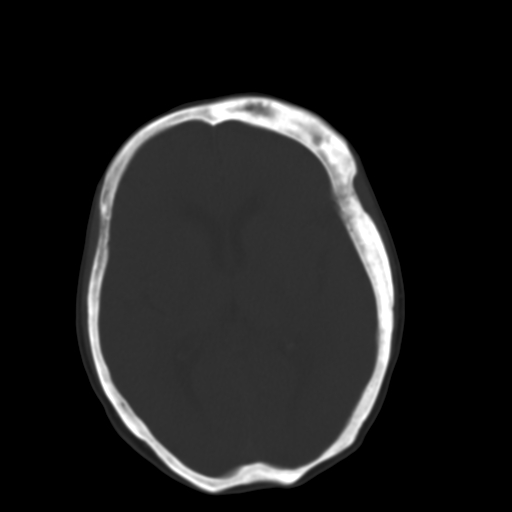

标题: CT17003:F58Y,骨纤维异常增殖征 [打印本页]

标题: CT17003:F58Y,骨纤维异常增殖征

女58y 头晕就诊

左侧额骨增厚,板障层密度增高。 支持骨纤维异常增殖症  。